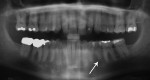

Five cases met the criteria as set forth in the study and are summarized in Table 1; radiographs of the five cases are shown in Figure 1 through Figure 21. Ages ranged from 15 to 48 years. Four patients were male and one female. All five cases involved Caucasian patients. Two cases involved the distal roots of mandibular first molars bilaterally (Figure 1, Figure 2, Figure 3, Figure 4, Figure 5, Figure 6, Figure 7, Figure 8, and Figure 18, Figure 19, Figure 20, and Figure 21); one case involved both roots of the mandibular first molars bilaterally (Figure 11, Figure 12, Figure 13, Figure 14); and two cases involved the mandibular second premolar unilaterally (Figure 9 and Figure 10, and Figure 15, Figure 16, and Figure 17). Two of the patients presented with symptoms similar to cracked-tooth syndrome (Table 1, Case 3 and Case 4), one with “chronic reversible pulpitis” (Table 1, Case 1), and two were asymptomatic (Table 1, Case 2 and Case 5).

Patients in all five cases exhibited PARR of the involved roots, as previously described (Figure 1 through Figure 21).40 The roots showed shortening and blunting of the apex of greater than 2 mm in all five cases. In three of the five cases, the PARR self-arrested without any treatment. The mandibular left first molar in Case 1 (Figure 5, Figure 6, Figure 7, and Figure 8) received conventional root canal therapy (RCT), while the mandibular right first molar in Case 3 (Figure 11, Figure 12, Figure 13, Figure 14) received a bonded ceramic crown. The PARR appears to have arrested in these two cases, and the outcome of the treatment in relation to the resorption could not be determined. The symptoms the patients were experiencing did eventually resolve. Consequently, all five study cases became symptom-free, including the patient who received conventional RCT (Case 1).

The Case 1 patient, who was the son of the Case 2 patient, was observed in preoperative orthodontic records prior to initiating orthodontic therapy (Figure 1 and Figure 2). The Case 1 patient also demonstrated PARR of the mandibular anterior incisors post-orthodontic therapy (Figure 8). The Case 5 patient had serial extractions completed as a child, but no fixed or removable orthodontic appliances were utilized. Past medical histories were all noncontributory (Table 1). No cases of MICR or MIAR were identified in any of the files reviewed.

The radiologic feature of PARR is characteristic of LIAR. PARR was readily apparent in all five cases (Figure 1 through Figure 21). Two or more millimeters of apical root were resorbed and replaced with normal-appearing trabeculated bone. The PDL space and remnants of the lamina dura appeared to be intact. The apical root canal space appeared patent but somewhat narrowed. The teeth were not ankylosed. Conversely, PARR due to trauma results in ankylosis with bone replacement resorption from both the apical and lateral directions of the root with obliteration of the root canal space and PDL space.1,40-42 PARR from orthodontics would be impossible to distinguish from LIAR radiographically; however, a history of prior orthodontics and the location of the involved teeth would separate this process from LIAR (Table 2).